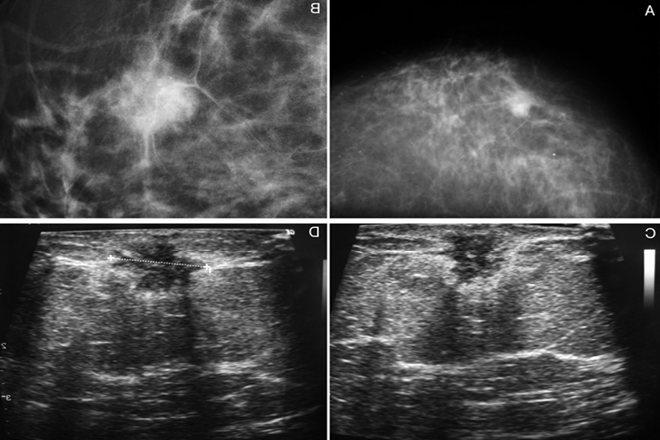

La mastografía es hasta ahora el mejor método de detección, tiene una sensibilidad diagnostica de 80 a 95%, aunque 10 a 15% de los tumores puede ser oculto sobre todo en mujeres con mamas densas (con el uso de mastografía digital mejora la sensibilidad diagnostica en este grupo de pacientes). El ultrasonido es en algunos casos una herramienta complementarios para diferenciar masas quísticas sólidas, para caracterizar lesiones benignas y malignas y como guía para la realización de biopsias de lesiones no palpables. La imagen por resonancia magnética con gadolinio tiene sensibilidad diagnostica de 94 a 100%, pero baja especificidad (37 a 97%) y valor predictivo positivo de 44 a 96%.

El fundamento del diagnóstico del cáncer de mama es la confirmación histológica del mismo, para esto se prefiere la realización de biopsias de mínima invasión, que permite determinar factores pronósticos y predictivos para el manejo integral de las pacientes.

El procedimiento de elección es la toma de biopsias con aguja de corte (trucut) tanto en lesiones palpables como en las no palpables; esta forma diagnostica se asocia con una exactitud del 98.5%.

En lesiones no palpables, la biopsia debe ser realizada bajo la guía de algún método de imagen (ultrasonido, mastografía, resonancia, etc.). Las biopsias quirúrgicas previo marcaje.